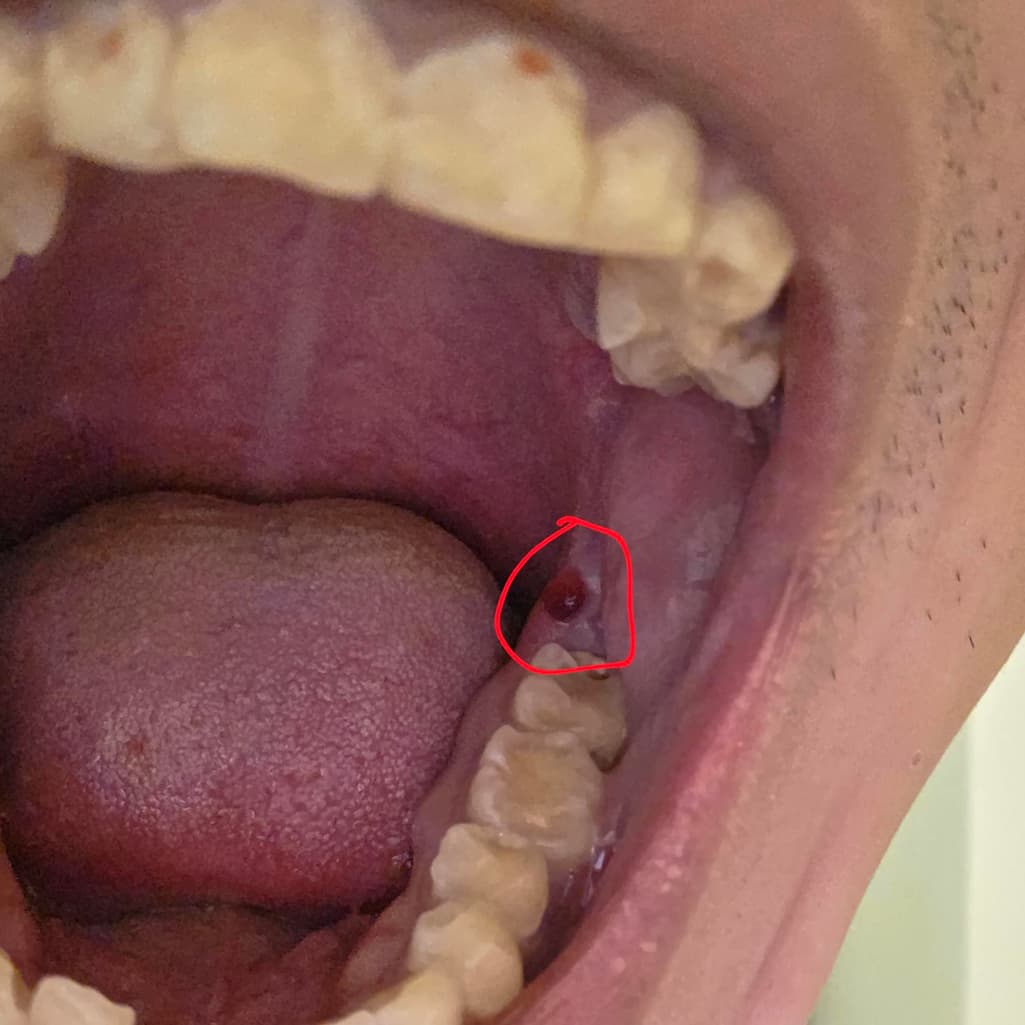

입 안쪽 붉게 상처난 부분 구강암일까요?

입 안 붉게 되있는 부분 구강암일까요?

구내염이나 다른 입병 중에 저런 증상이 있는건가요?

피가 나지는 않고 저렇게 붉게만 되어있고 혀로 만져보면 느낌이 있습니다.

구강암 아닙니다. 단순 물집 수포 입니다. 잇몸에 상처를 입어서 이런 물집이 생깁니다. 저절로 터지니 그냥두면 됩니다. 혹시 터질 때 피가 조금 스며 나올 수도 있습니다.

사진에 보이는건 잇몸이 치아에 씹혀서 피가 고인거 같습니다. 그냥 터트리면 문제가 없으니 너무 걱정하지마세요.

악성병소 여부는 조직검사를 해봐야 합니다 눈으로 봐선 어떤 이유때문인진 모르겠지만 혈종이 생긴것으로 보입니다